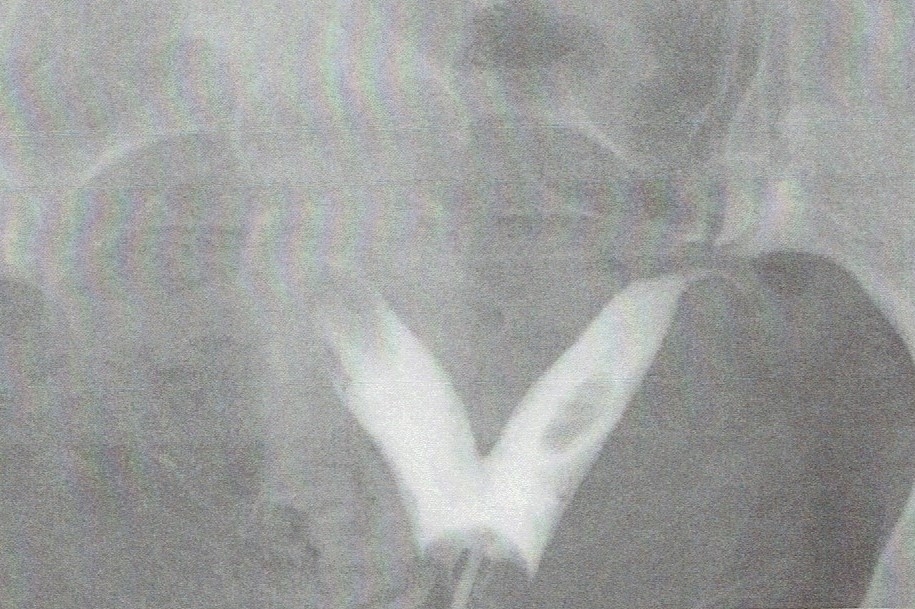

当クリニックでの子宮卵管造影検査では、確かに中隔子宮と、両側卵管閉塞を認めました。子宮鏡検査でも多発性のポリープを確認しています。(この方は甲状腺疾患もあったので、水溶性の造影剤を使用しているので、画像がやや薄いのです)

画像は、手術数ヶ月後のものです。中央の中隔は切除され、子宮内腔が整っています。

通常は、逆三角形ですが、これだけ切除されていれば十分なのですね。